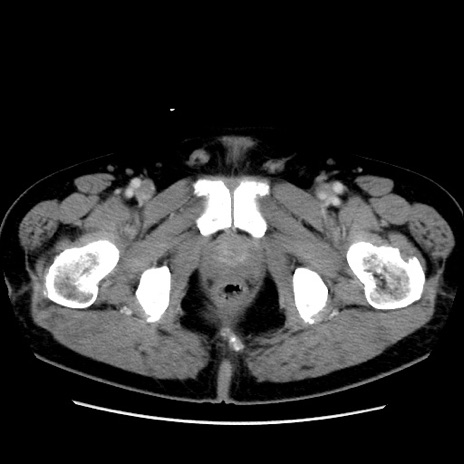

症例16(横断像)

【症例】 70歳代男性

【主訴】 腹痛、嘔吐

【現病歴】 約1ヶ月前より間欠的に腹痛と嘔吐あり、当院消化器内科を受診したところCTで多発する肝臓のLDAを指摘され、精査中であった。以降は消化器症状は安定していたが、2日前より嘔気と腹痛があり、同日より排便・排ガスが消失した。改善認めず、 本日、救急外来を受診した。

【既往歴】 大腸ポリープ切除後。

【身体所見】意識清明・会話良好、BT 36.3℃、BP 127/80mmHg、 P 80bpm、腹部:膨満あり、平坦・軟、上腹部正中および下腹部正中に圧痛あり、反跳痛なし、筋性防御なし。

【データ】WBC 7200、CRP 0.77